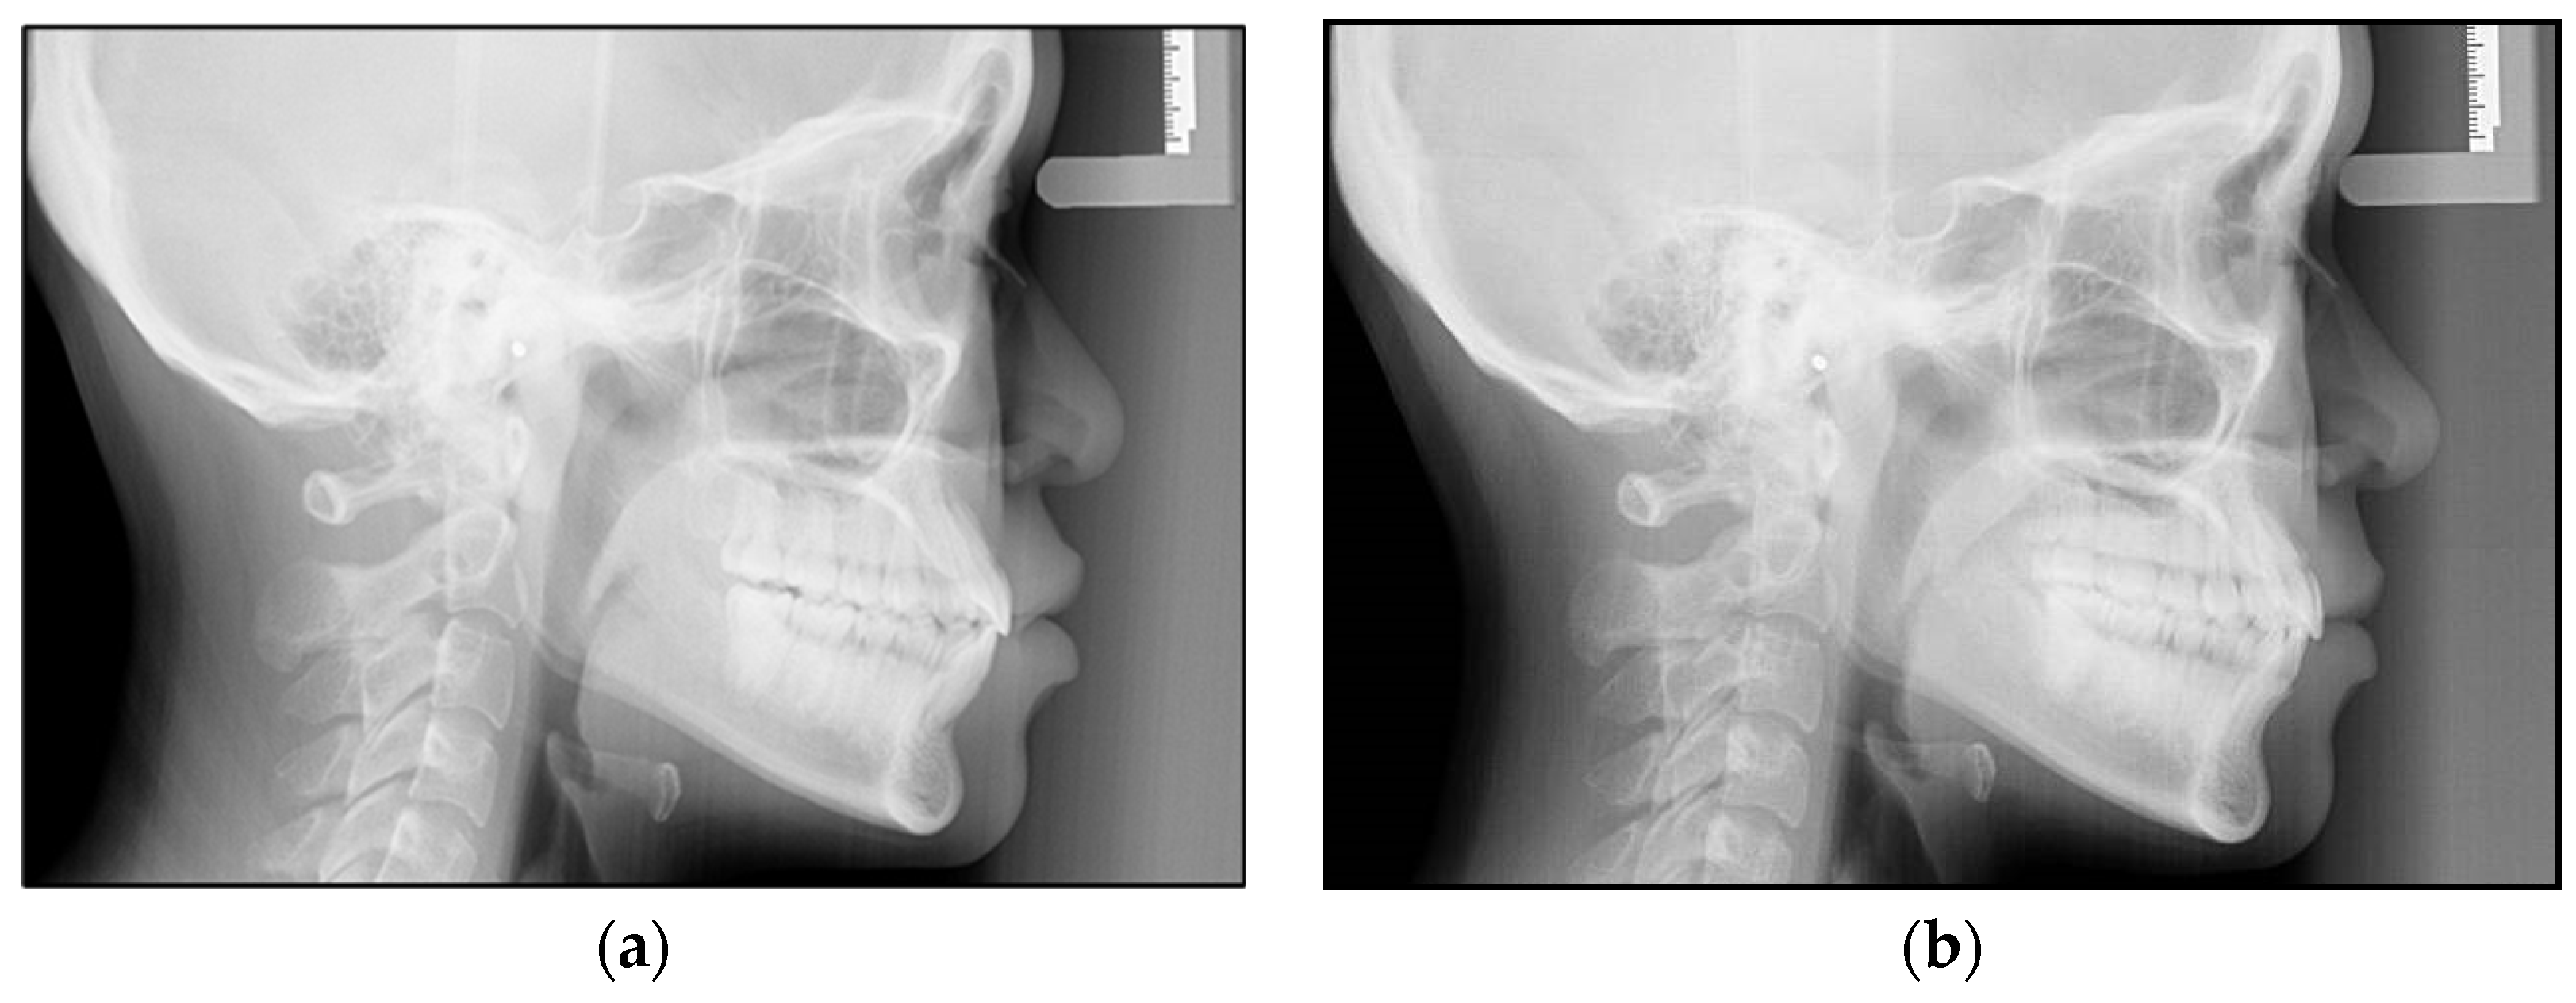

In total, 28 lateral cephalometric radiographs of the subjects were considered in this study. All the cephalometric radiographs were taken using a digital cephalometer (Orthopanmograph OP 200D, Instrumentarium Dental, Tuusula, Finland). The digital images were stored in a computer database with the manufacturer’s software and imported into Adobe Photoshop CS software (version 20). The software was used to resize the digital photos to a 1:1 ratio, and the images were printed using a 4800 dpi inkjet color printer (Canon PIXMA G4010, Canon Inc., Tokyo, Japan) on 180 gsm glossy inkjet photo paper made for high-quality photographic images. The cephalometric radiographs that were collected at the beginning were defined as Pretreatment (T0) and those at the end of the first series of Invisalign treatment were defined as Posttreatment (T1) (Figure 1a,b).

Figure 1. (a,b) Lateral cephalometric radiographs of a patient at the beginning of the treatment (a) and after treatment with the first series of Invisalign (b).